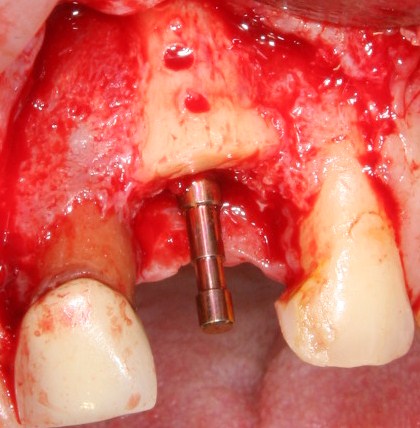

Прежде, чем приступить к аугментации (пластике) лунок зубов, мы подготовили лунки для имплантатов. В таких клинических случаях нет необходимости в использовании шаблона. Вместо этого, мы применяем общепринятые правила позиционирования и соблюдаем рекомендации производителя по хирургическому протоколу:

В процессе ирригации лунки промываются, что позволило нам еще раз подтвердить ранее сделанные выводы. С помощью аналогов имплантатов, входящих в хирургический набор Xive, мы проверили возможность стабилизации имплантатов в будущих лунках. Исходя из правил подбора и позиционирования имплантатов (я очень рекомендую почитать об этом здесь>>) мы остановились на Xive S диаметром 3,4 мм и длиной 13 мм.

Сначала мы провели и зафиксировали деэпителизированный соединительнотканный аутотрансплантат (ССТ). Для этого мы сформировали тоннель и использовали ортодонтическую проволоку в качестве проводника. Подробнее об этой методике можно почитать здесь>>.

Затем уложили ксенографт. Особенностями Bio-Oss Collagen являются удобство адаптации, устойчивость к вымыванию и выдавливанию, поэтому мы просто уложили полученные ранее пирамидки вестибулярно относительно будущего имплантата, после чего прижали их с помощью уже упоминавшихся аналогов имплантата, входящих в хирургический набор имплантационной системы Xive (кстати, при работе с другими имплантационными системами для паковки графта в лунке можно использовать круглые остеотомы для синуслифтинга).

Установка имплантатов

По ряду уже упомянутых выше причин, для решения этой клинической задачи мы выбрали имплантаты Xive. Лунки для них мы уже приготовили. возможную первичную стабильность оценили. Имплантаты мы установили с усилием чуть больше 15-20 Нсм — такого крутящего момента более, чем достаточно, особенно если учесть, что временные коронки будут соединяться между собой.

Подробно о том, что такое крутящий момент и хирургический протокол можно прочитать здесь>> и тут>>, соответственно. Из-за использования специальных индивидуализируемых временных абатментов, имеющих только три положения, нам нужно позиционировать платформу имплантатов по граням. Это очень просто  — мы выводим вырез абатмента TempBase (он входит в комплект поставки) вестибулярно.

После перкуторной проверки стабильности имплантатов и точности позиционирования, мы переходим к следующему этапу — сохранению десневого контура.

Установка имплантатов занимает около двух минут.